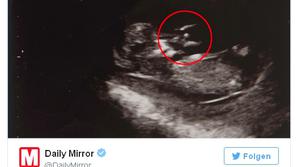

Magazin Angel na ultrazvoku? Britanka Jennifer Holman je prepričana, da je na ultrazvočnem posnetku angel.